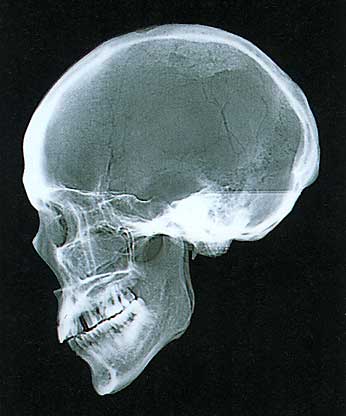

古墳時代人男性

(標本・国立科学博物館/撮影・神奈川歯科大学放射線科)